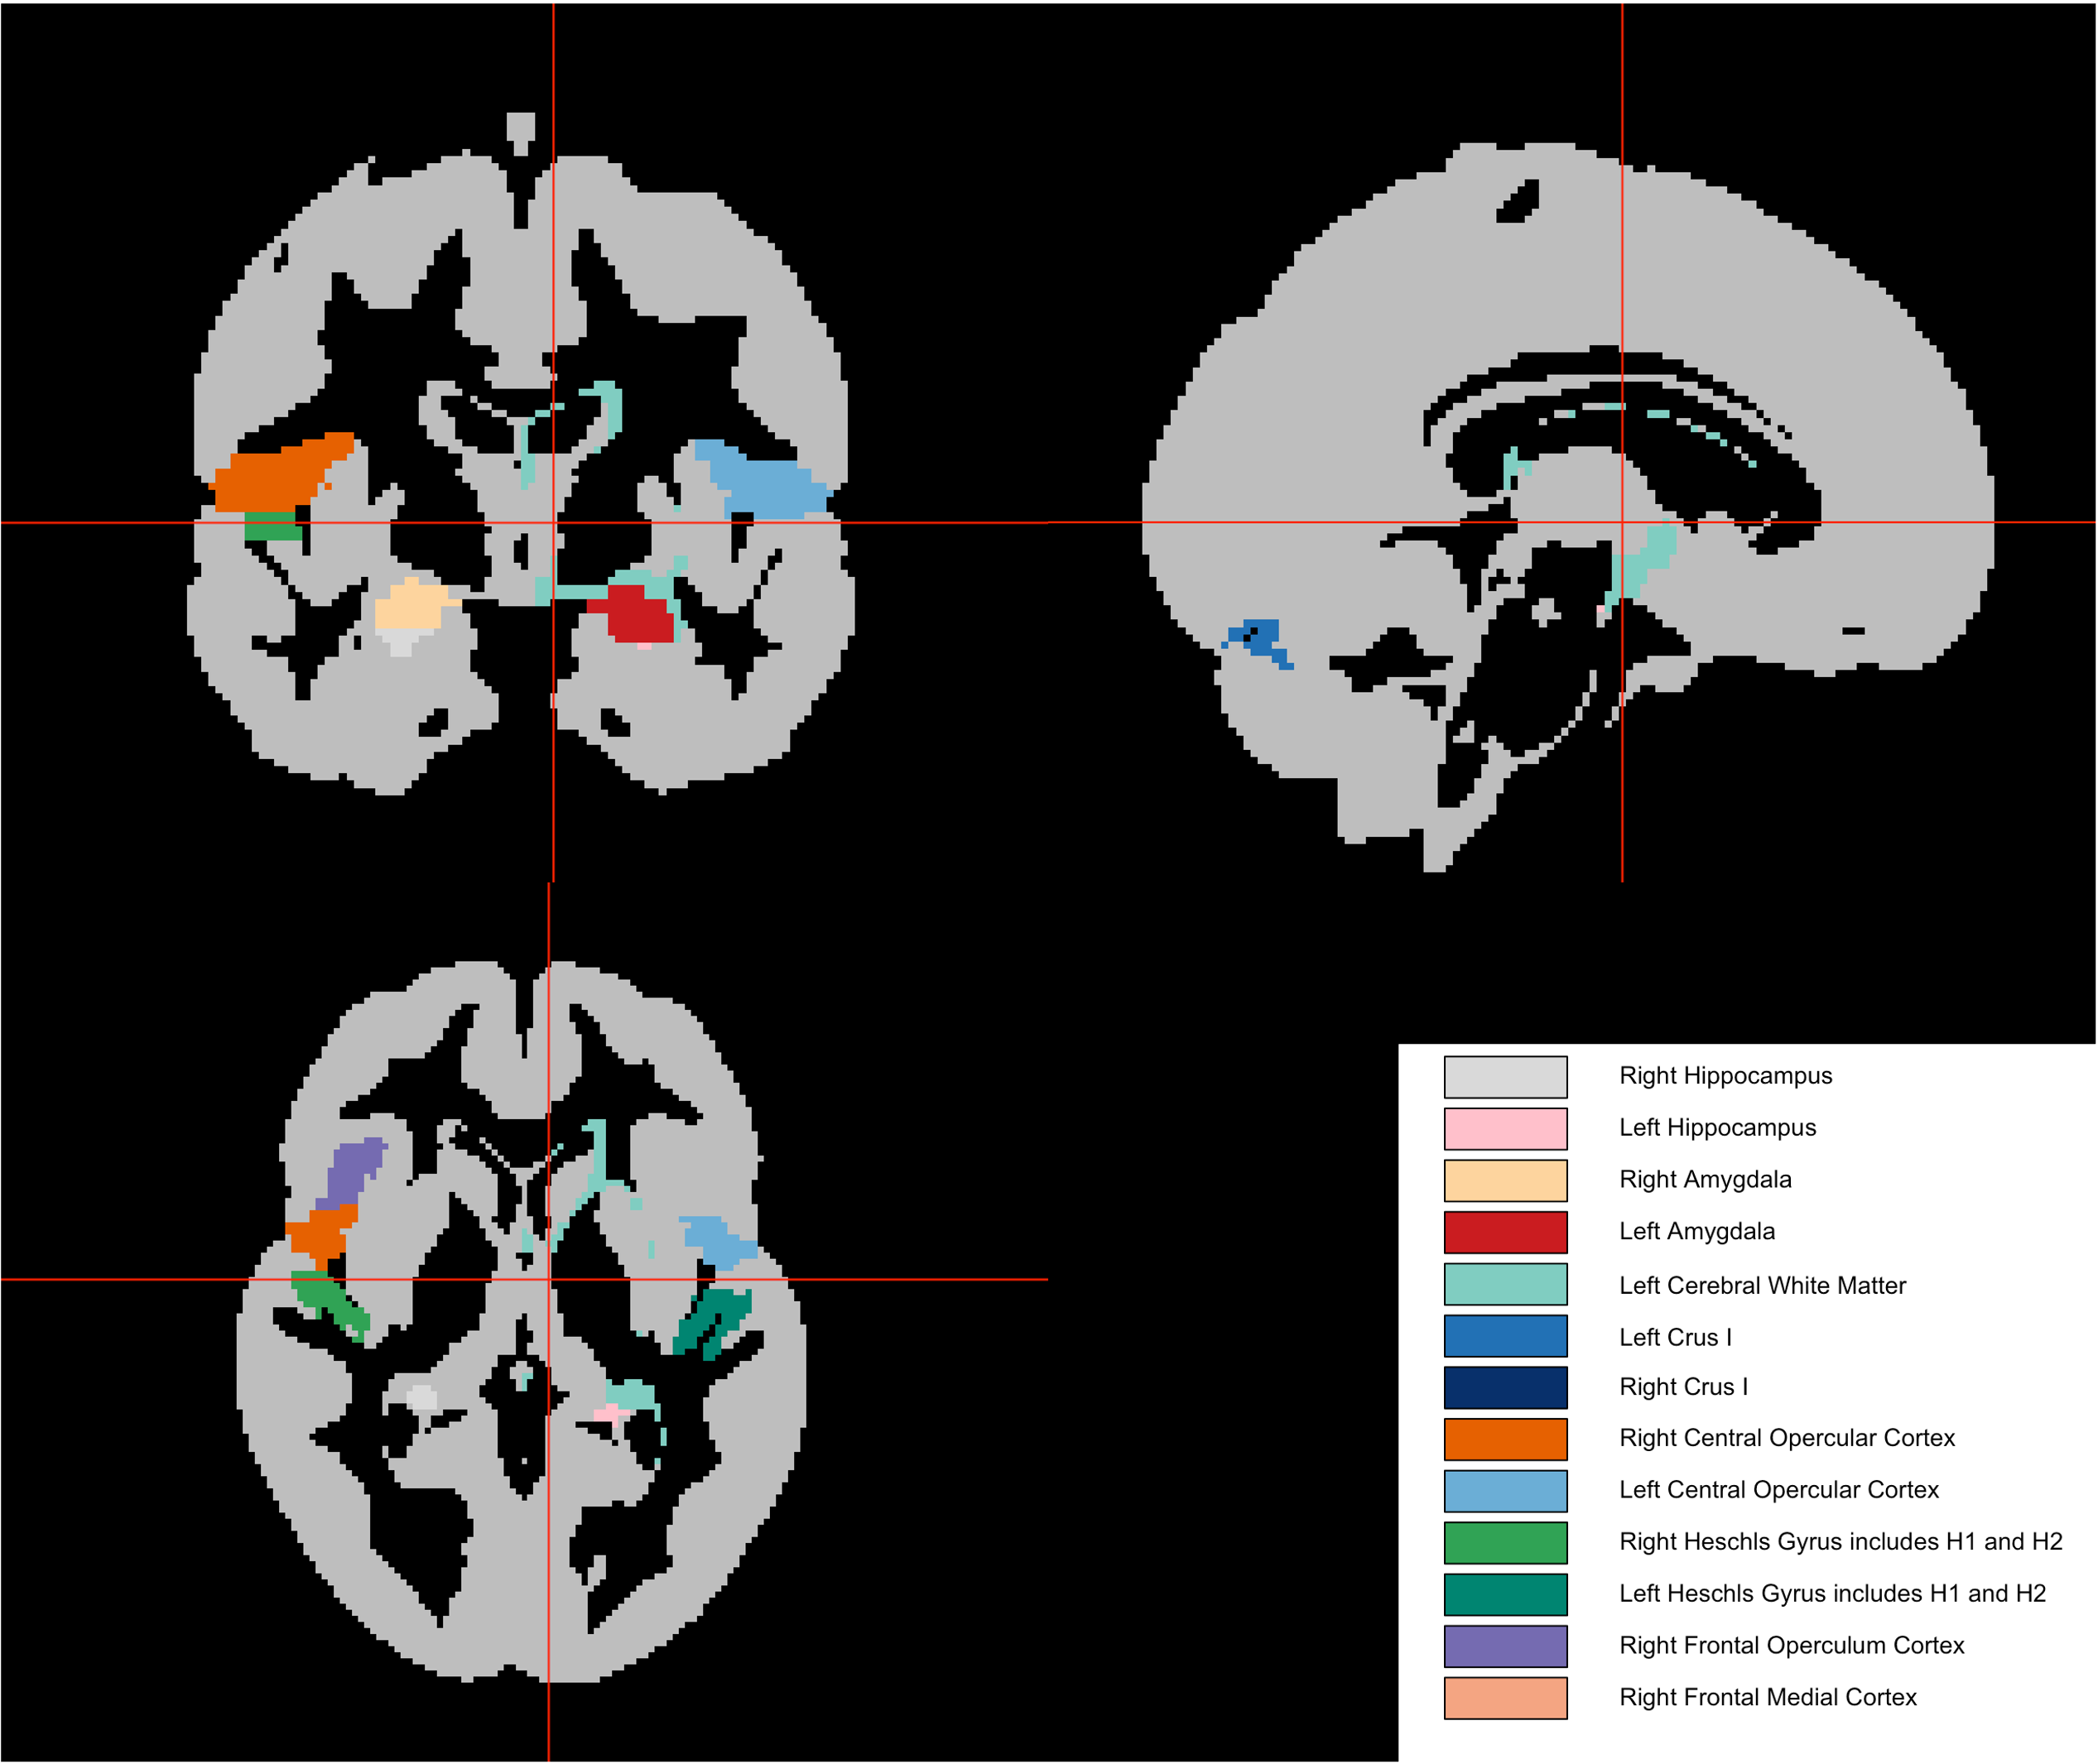

The team also examined which brain regions contributed most to the prediction. Areas such as the hippocampus and amygdala — regions previously linked to mood and emotion — showed signals consistent with earlier research. However, no single brain region stood out strongly enough to act as a clear marker on its own.